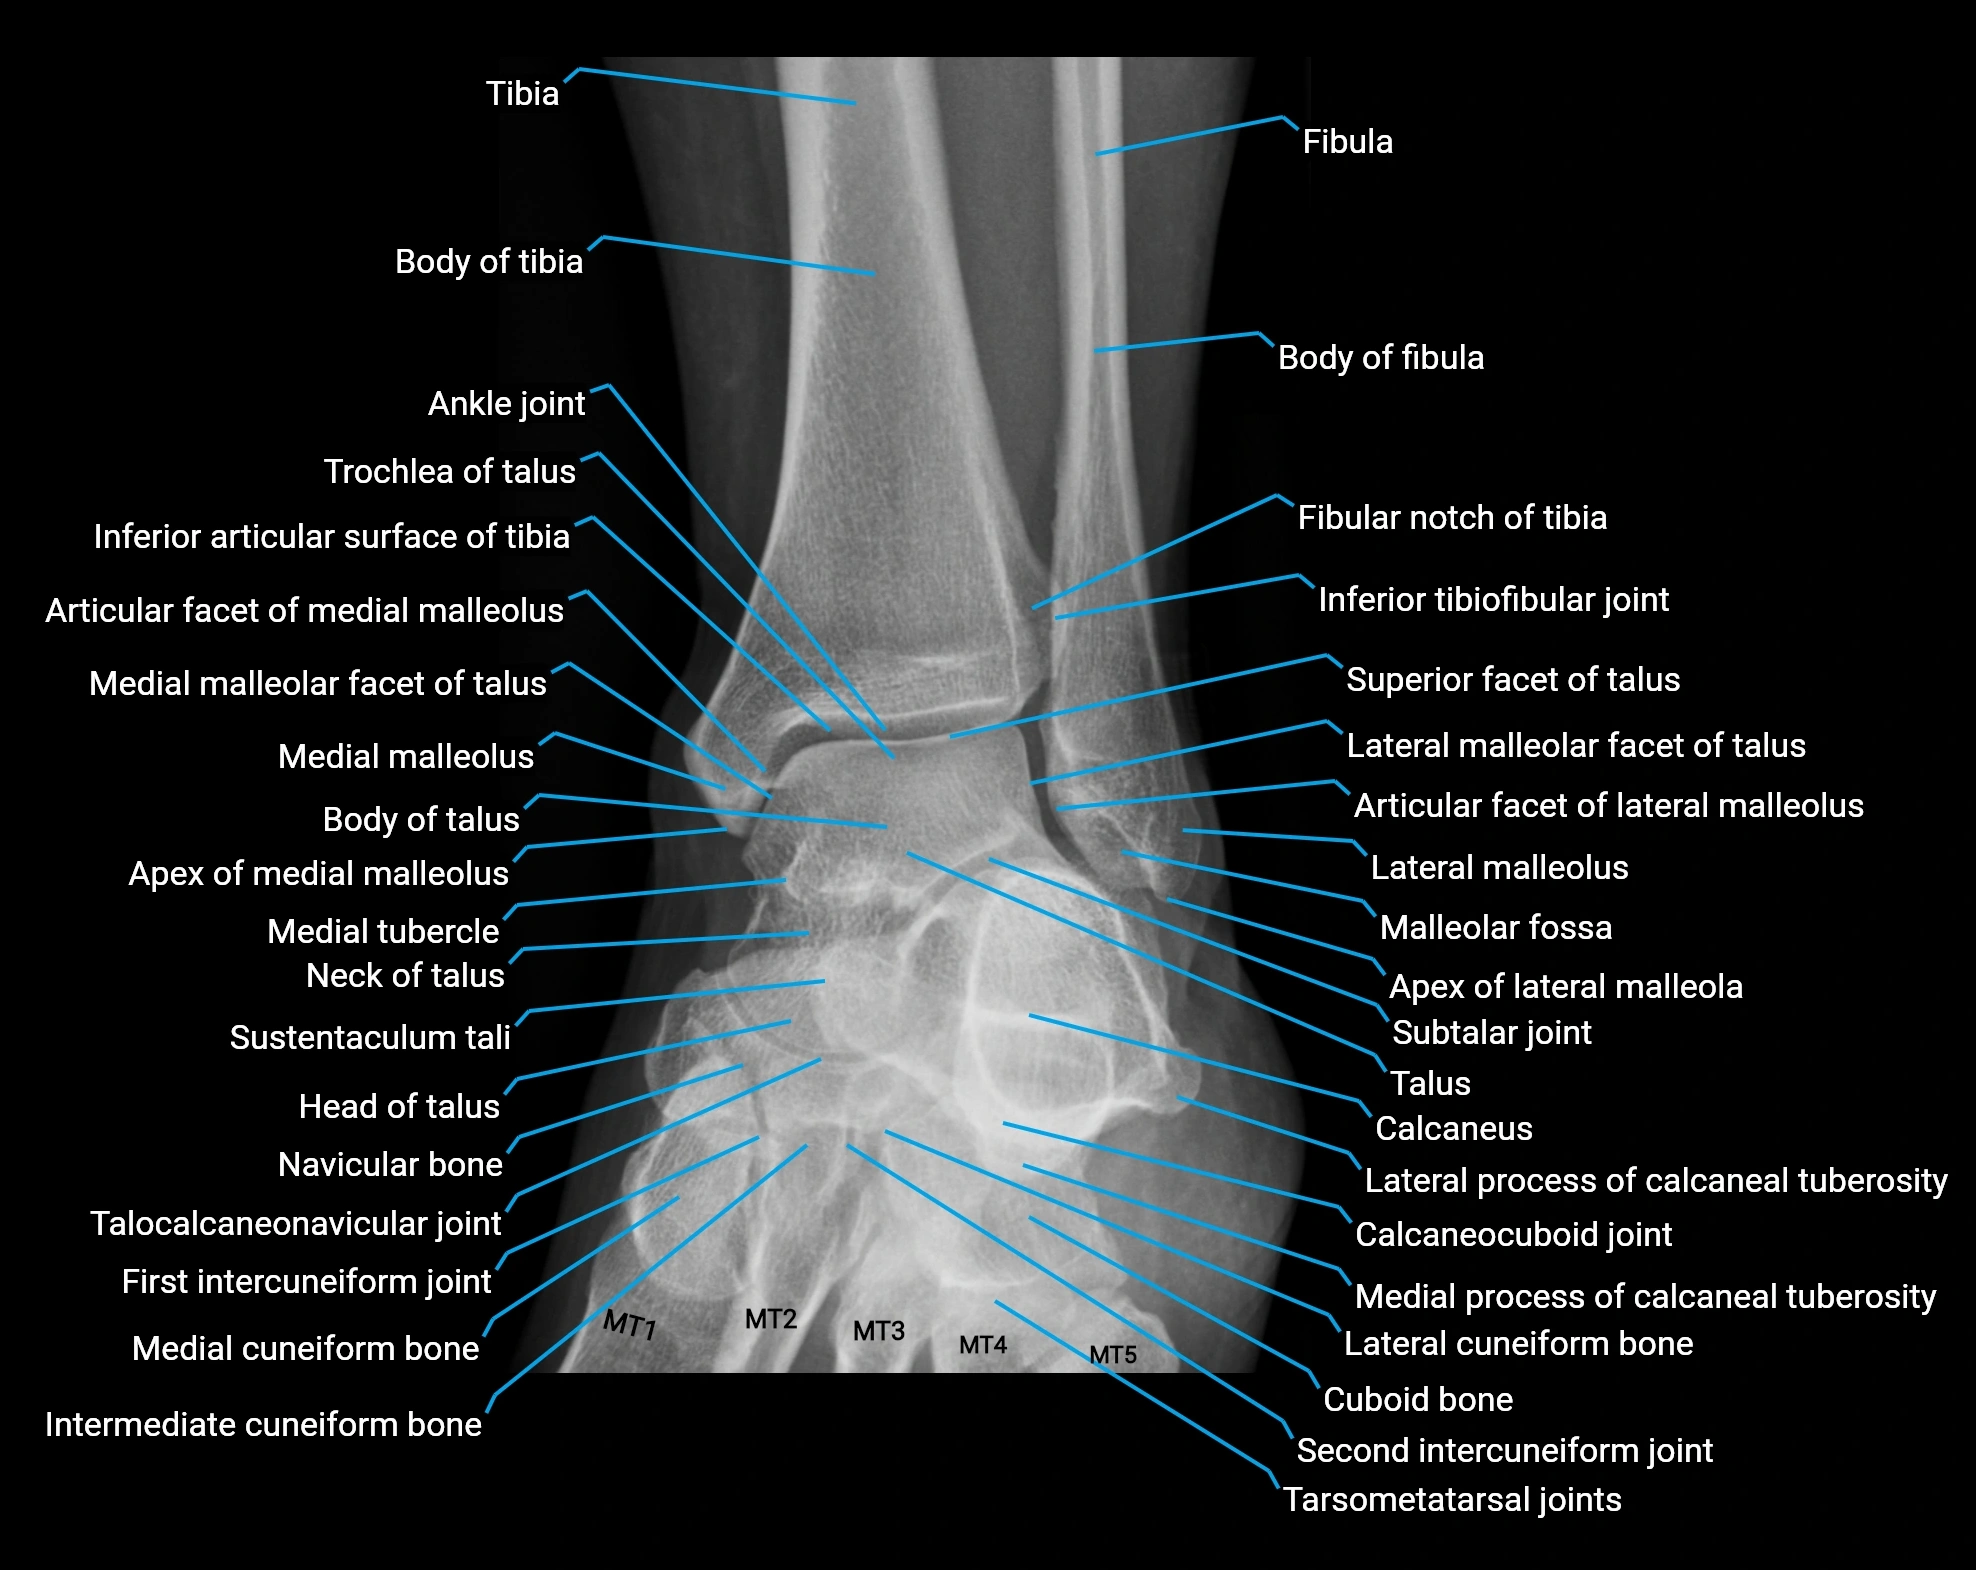

- Ankle joint

- Body of tibia

- Calcaneus

- Fibula

- Fibular notch of tibia

- First intercuneiform joint

- Inferior articular surface of tibia

- Inferior tibiofibular joint

- Intermediate cuneiform bone

- Lateral cuneiform bone

- Lateral malleolus

- Malleolar fossa

- Medial cuneiform bone

- Medial malleolar facet of talus

- Medial malleolus

- Medial process of calcaneal tuberosity

- Navicular bone

- Second intercuneiform joint

- Subtalar joint

- Superior facet of talus

- Sustentaculum tali

- Talocalcaneonavicular joint

- Tarsometatarsal joints

- Tibia